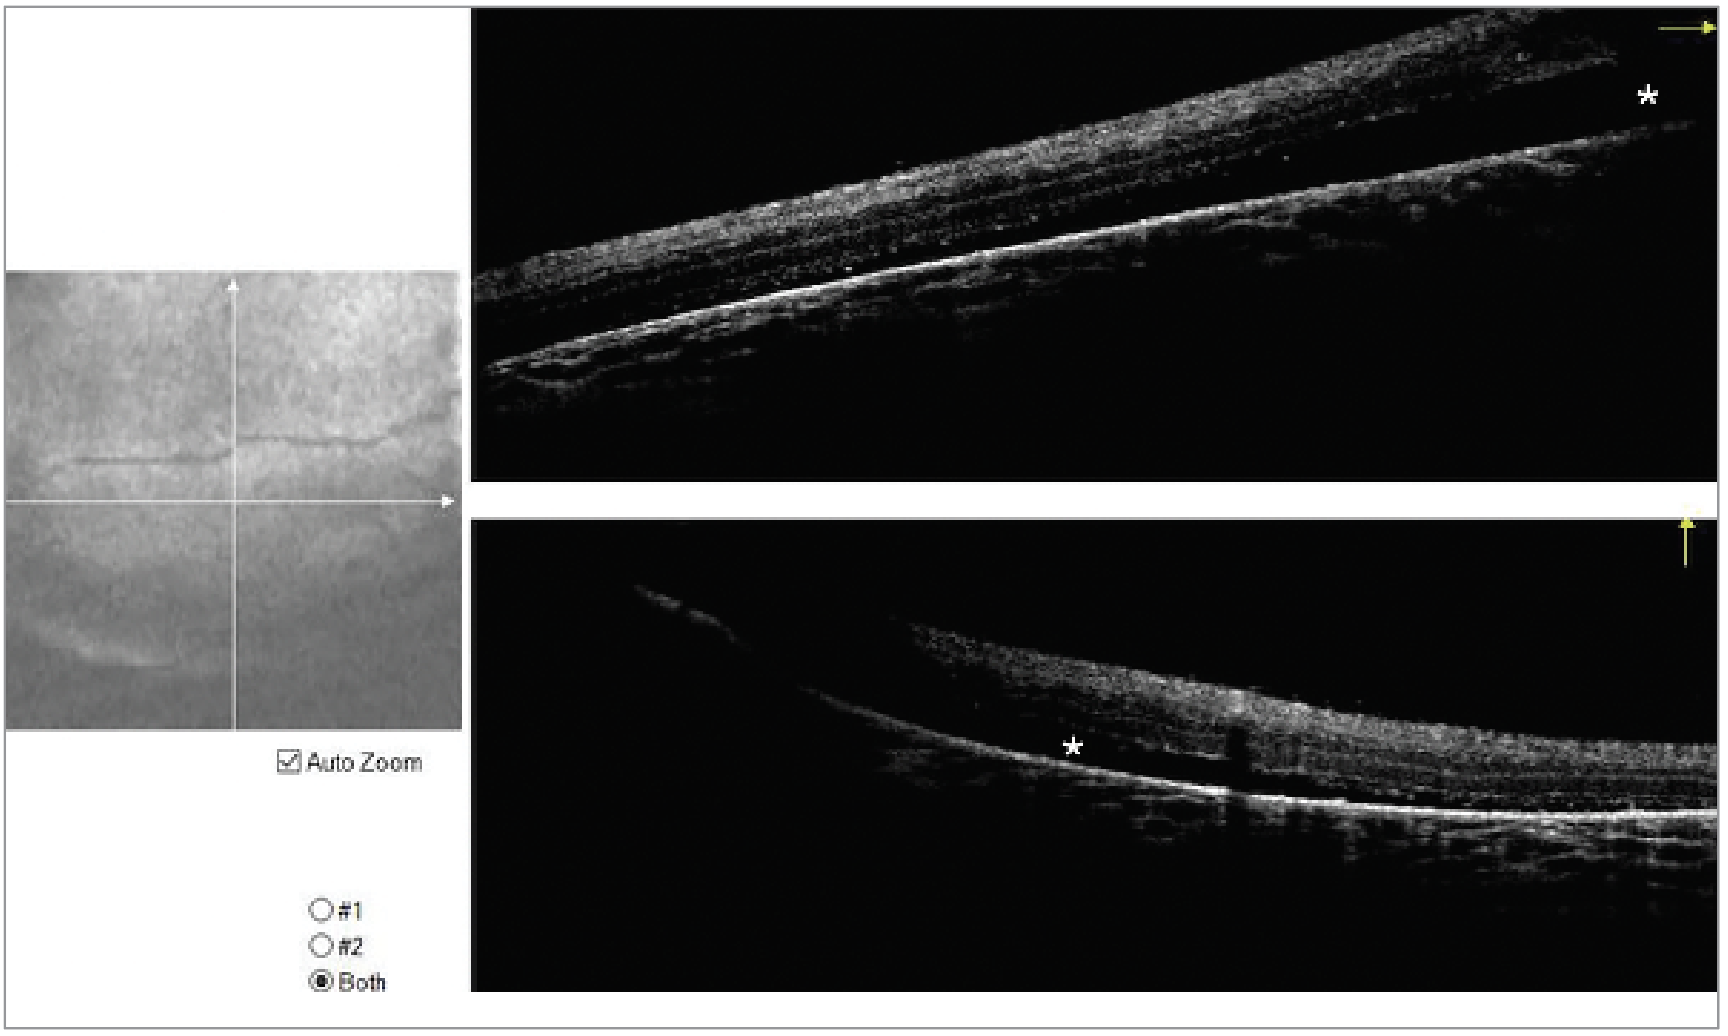

There was subretinal fibrosis and shallow, low lying temporal subretinal fluid. OCT confirmed shallow temporal subretinal fluid (Figure 2).

Intraoperative B scan ultrasonography revealed a large peripapillary staphyloma with cyst (Figure 3).

Figure 2 . Intraoperative OCT of the left eye demonstrating shallow subretinal fluid in the temporal macula. |